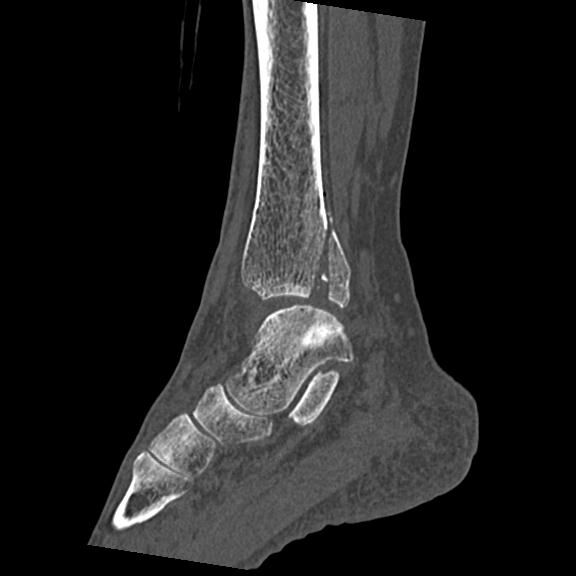

102755 1/4 2R 1/15 2R 右足関節 68歳女性 右三果脱臼骨折